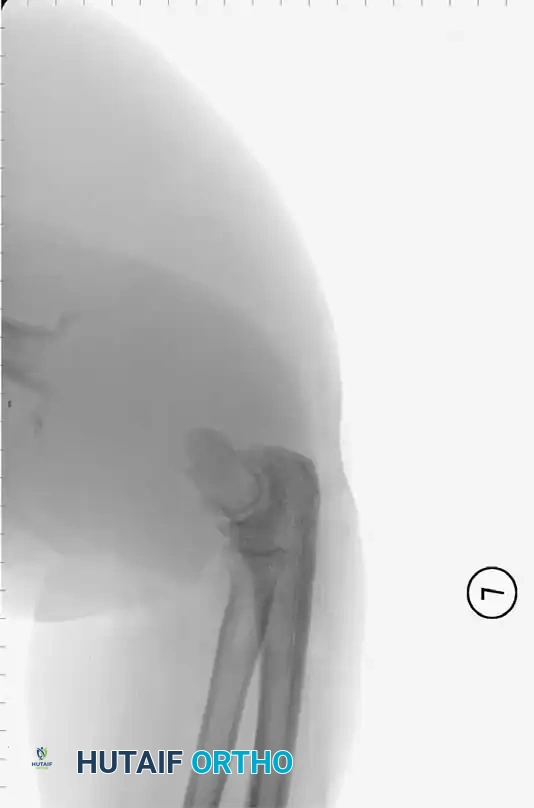

Plain Radiography

Plain radiographs are the mandatory first step in imaging but are notoriously insensitive in the acute phase. Early findings may only show soft-tissue swelling or obliteration of normal fat planes.

* Bone Destruction: Bony changes (periosteal reaction, osteopenia, or focal lysis) are not apparent on plain films until the infection has been present for 10 to 21 days.

* Matrix Loss: Furthermore, 30% to 50% of the regional bone matrix must be destroyed before a lytic lesion becomes radiographically visible.

Image

Fig. 15-1 Anteroposterior (A) and lateral (B) radiographs demonstrating advanced bone destruction and periosteal reaction typical of subacute to chronic osteomyelitis.

While fewer than 5% of plain radiographs are abnormal at initial presentation, and fewer than 30% at 1 week, up to 90% will demonstrate abnormalities by 3 to 4 weeks. Arthrography can be utilized to document proper intra-articular needle placement during aspiration; however, contrast dye should only be injected after synovial fluid is obtained, as the bactericidal properties of iodinated contrast can yield false-negative cultures.